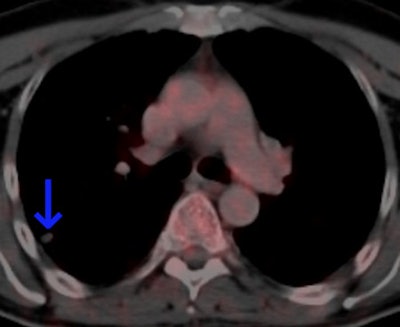

This 62-year-old melanoma patient has a 10-mm metastasis in the right upper lobe. The CT image (left) failed to show increased tracer uptake on the F-18 FDG PET image (right). All images courtesy of Dr. Marius Mayerhoefer.

The same patient as seen with the fused color-coded PET/CT image.F-18 FDG PET can help in the workup of pulmonary nodules because it reflects the tissue glucose metabolism, which is elevated in most malignant lung lesions. But mainly due to its limited spatial resolution, the sensitivity of PET for detecting pulmonary metastases is only moderate: In melanoma patients, it is between 57% and 70%, according to Mayerhoefer.